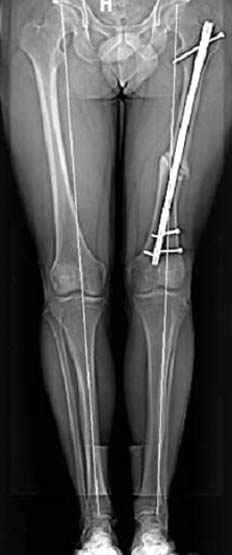

Несколько снимков из моей коллекции, чтобы разьяснить, почему мы до сих пор делаем различные варианты остеотомии.

N3 рисунок окончательный снимок, после операции моя рентгенограмма должен выглядеть примерно как эта картина. На N4 снимке клин перед удалением; N5 послеоперации 3 нед.; N6 окончательная рентгенограмма.

варус при проксимальном отделе 95 градусной пластиной.

пластическая модель; и коррекция бедра аппаратом Илизарова.